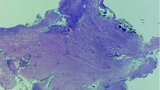

Fig. 20: Tissue removed from the endodontic space three months after transplantation (H&E stain; 2× magnification).

Fig. 21: Tissue removed from the endodontic space three months after transplantation (H&E stain; 4× magnification).